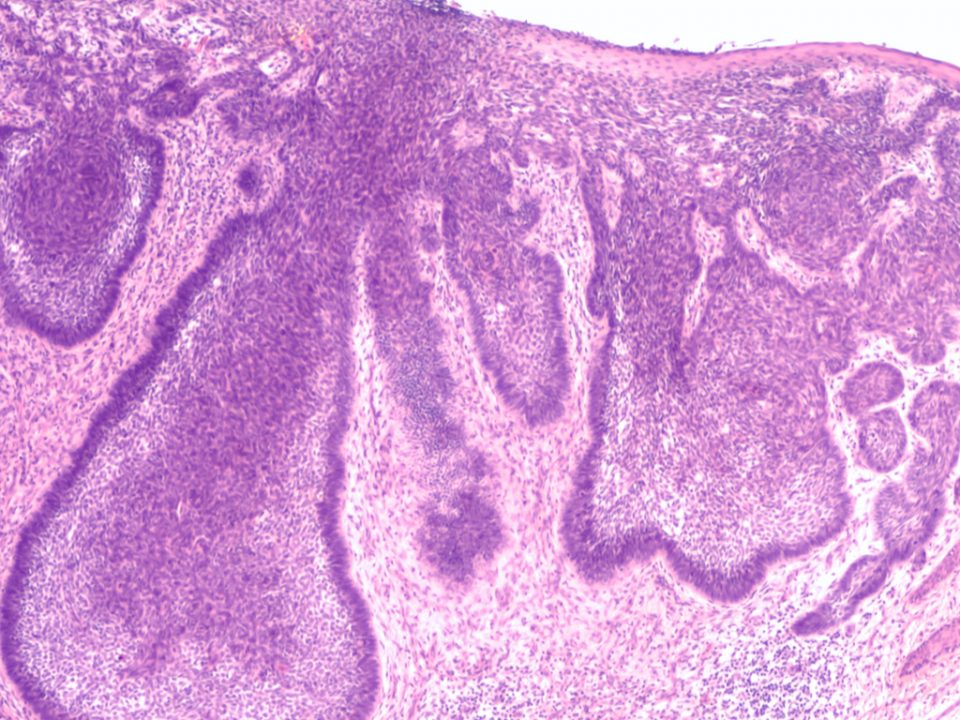

El cáncer de piel, en función de sus diferencias epidemiológicas y pronósticas, se divide principalmente en dos tipos: melanoma cutáneo y cáncer cutáneo no melanoma, que […]

Como cualquier otro cáncer, el melanoma se estadía en función de una serie de parámetros que indican su gravedad y posteriormente se establece un pronóstico y […]